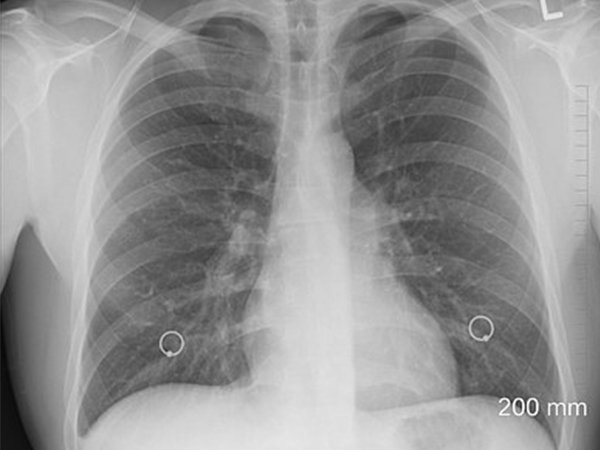

எப்படி கண்டுபிடிப்பது?

சேதமடைந்த மூச்சுக்குழாய் வழியாக காற்று நுழைவதால் கிருமிகள் மற்றும் சளி போன்றவை நுரையீரலில் சேரத் துவங்குகிறது. இதன் காரணமாக அடிக்கடி தொற்று பாதிப்பு மற்றும் காற்றுப்பாதையில் தடை போன்றவை ஏற்படுகிறது.

இந்த நிலைக்கு எந்த ஒரு தீர்வும் இல்லாமல் இருந்தாலும், இதனை நிர்வகிக்க முடியும். இந்த அடைப்பை விரைந்து நிர்வகித்து சிறந்த முறையில் உடலுக்கு ஆக்சிஜென் பரவுவதை செயல்படுத்த வேண்டும்.